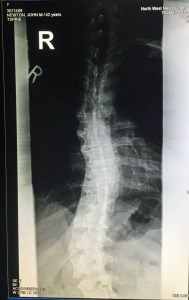

My latest target for medical help is my spine. My back resembles a melted candy cane and my peppermint stripes are all twisted, skull to pelvis. I’m in nerve pain daily up and down my back. Many times I can handle the pain with grace. Many times I cannot. So I wanted to know from an expert what can be done — beyond physical therapy — to alleviate my pain.

The visit with Dr. Luke Knox went great. He sent a lot of time talking to us, examining me, and showing us the 15 X-Rays they took of my back today, along with a recent MRI. I’ve found few doctors who will take ample time to attend to their patients and answer questions. A frustration I have with modern doctors is their tendency to ask 10 questions, hold up your arm, and then guess at what’s wrong with you. They see you for eight minutes, charge you $400 and leave you feeling disrespected in some way. But Dr. Knox was wonderful. Even when he repeatedly said, “That doesn’t look good.”

- My spinal issues might be hereditary. Dr. Knox asked us, “Do you have kids?” We said, “No. Not yet.” Then he asked, “Do you want kids?” We said, “Yes.” Then he told us to watch out for scoliosis in our children and get it treated as soon as possible when it is discovered. I asked whether there is a higher risk for our children and he said, “Yes.”

- My age is affecting my ability to recover. If I were 18, the doctor said, there might be a chance to correct my spinal flaws. But at 41, it is very unlikely that we can correct my back. My body doesn’t react as well to correction, so I guess you can say that I’m stuck in my ways! Ha!